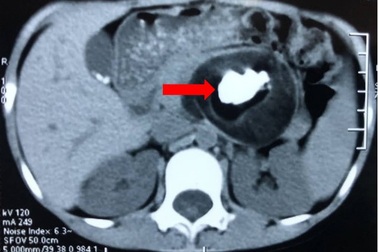

Phẫu thuật thành công ca cắt thận đầu tiên bằng phương pháp nội soiMột bệnh nhân ở phường Thạch Quý, TP Hà Tĩnh vừa được các bác sỹ Bệnh viện ĐK TP Hà Tĩnh phẫu thuật cắt bỏ thận trái thành công bằng phương pháp nội soi. Đây là ca phẫu thuật đầu tiên của tỉnh Hà Tĩnh bằng phương pháp nội soi.